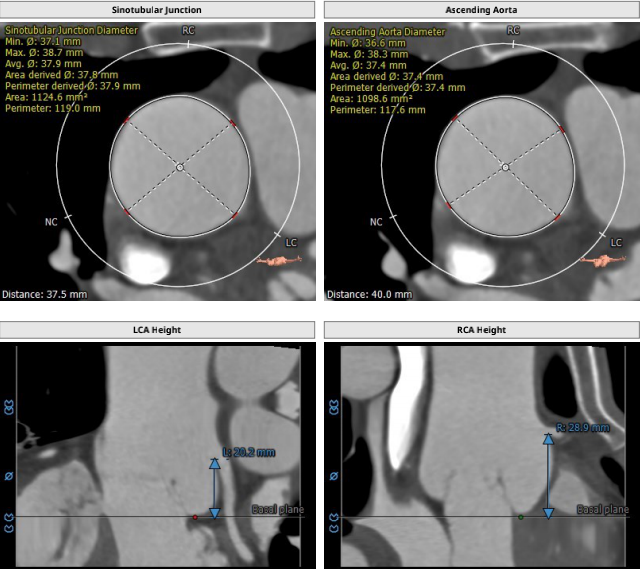

术前CT测量:

瓣环:27mm;LVOT:26.8mm;STJ:37.9mm;升主动脉:37.4mm;左冠高度:20.2mm;右冠高度:28.9mm;钙化积分:18mm3;瓣环与水平面夹角:29°;心尖入路夹角:108°。